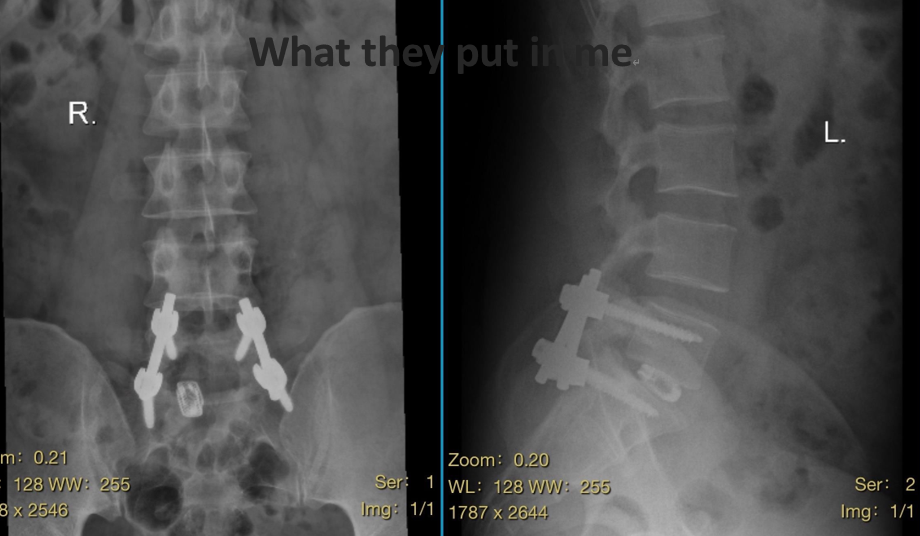

PLIF(Posterior Lumbar Interbody Fusion)是一种经典且成熟的腰椎后路融合术式,适用于椎间盘突出合并不稳或椎管狭窄的患者。其核心步骤包括:

3. 内固定稳定:

使用钉棒系统提供即刻稳定,为融合创造良好环境。

该术式能有效恢复椎间隙高度、重建脊柱稳定性,是治疗严重腰椎退变性疾病的可靠选择。